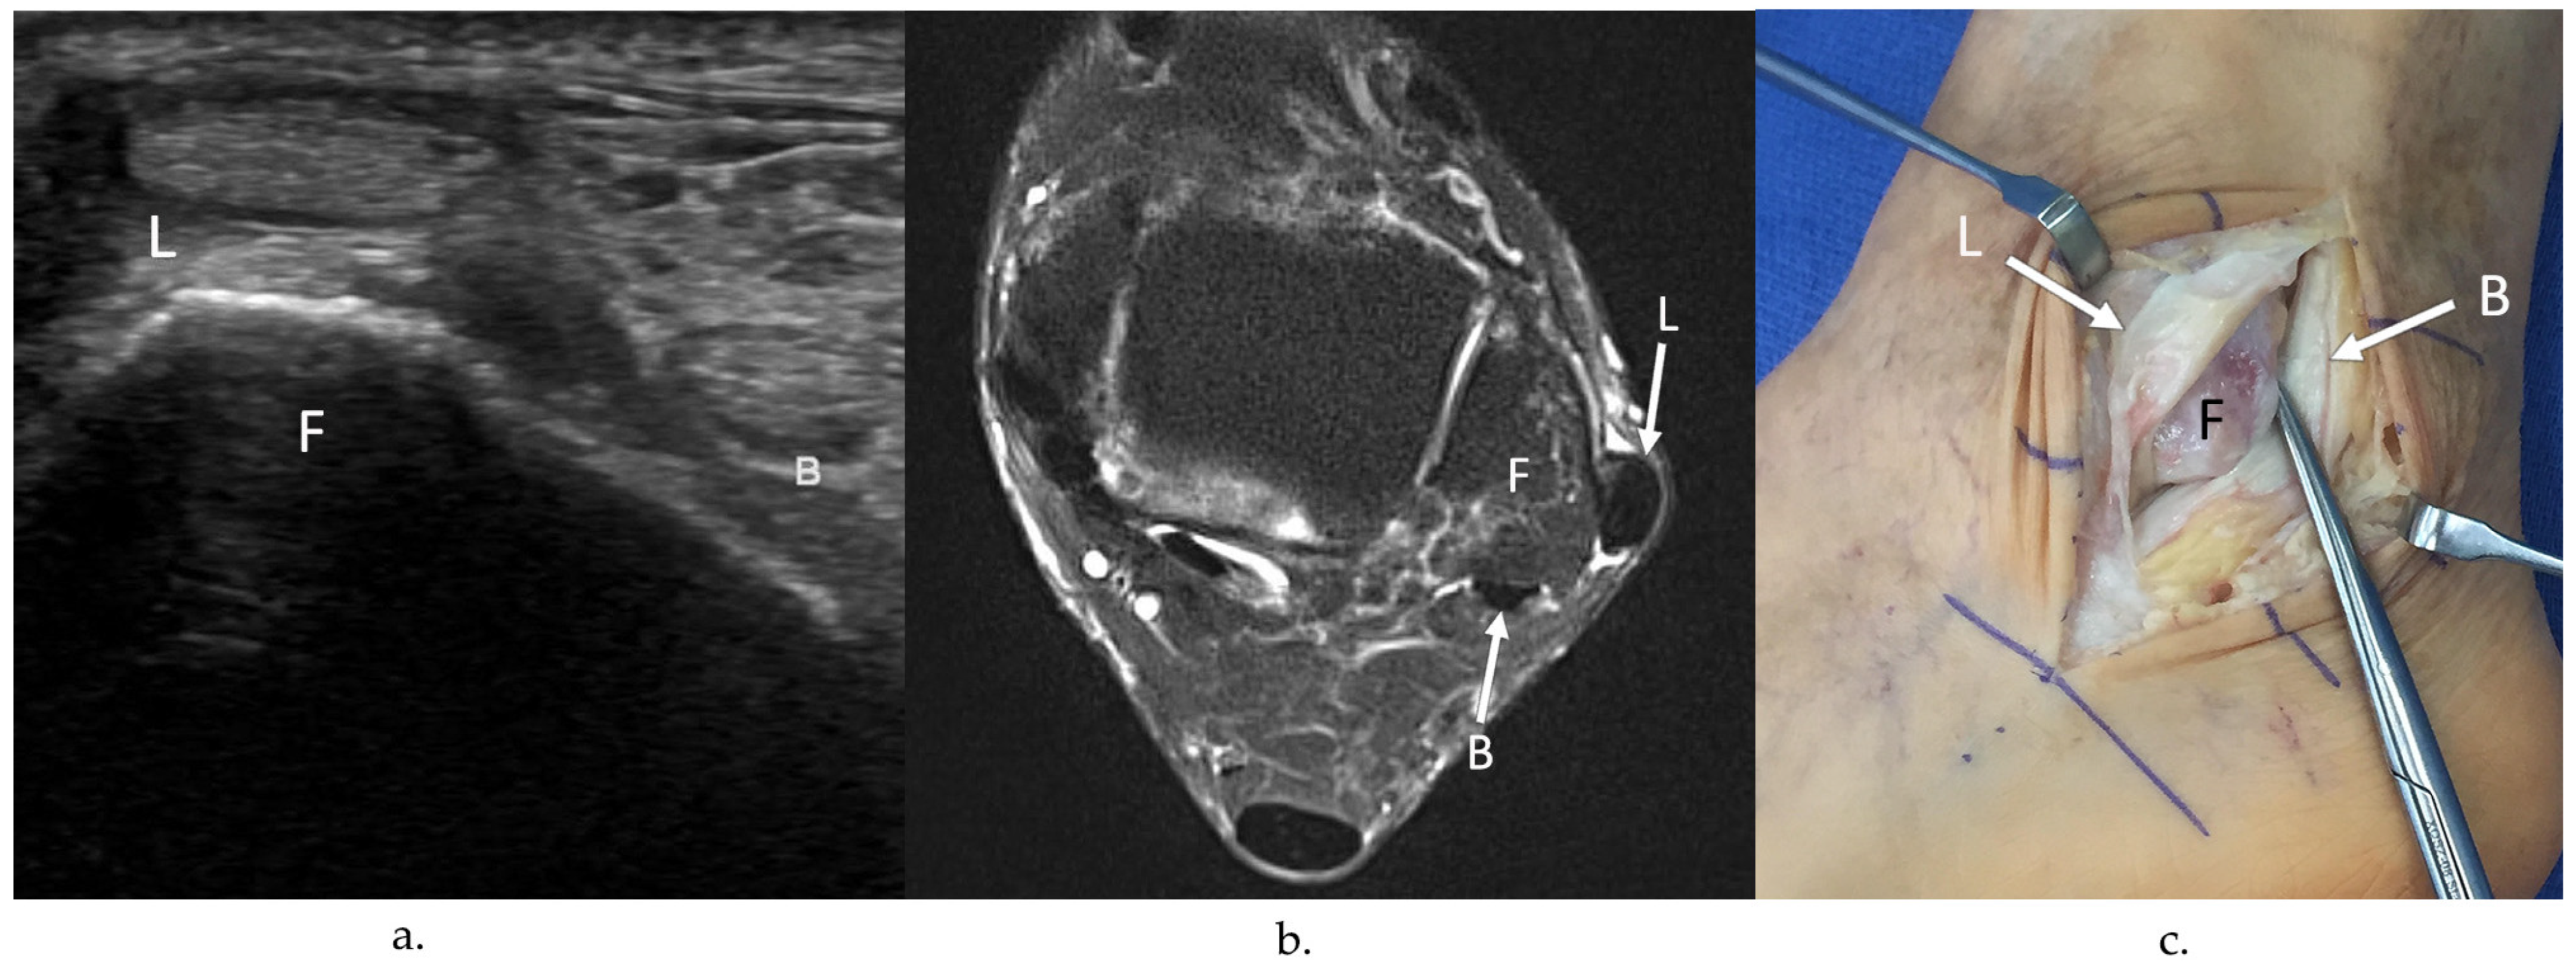

4.2. Peroneus Longus Tears